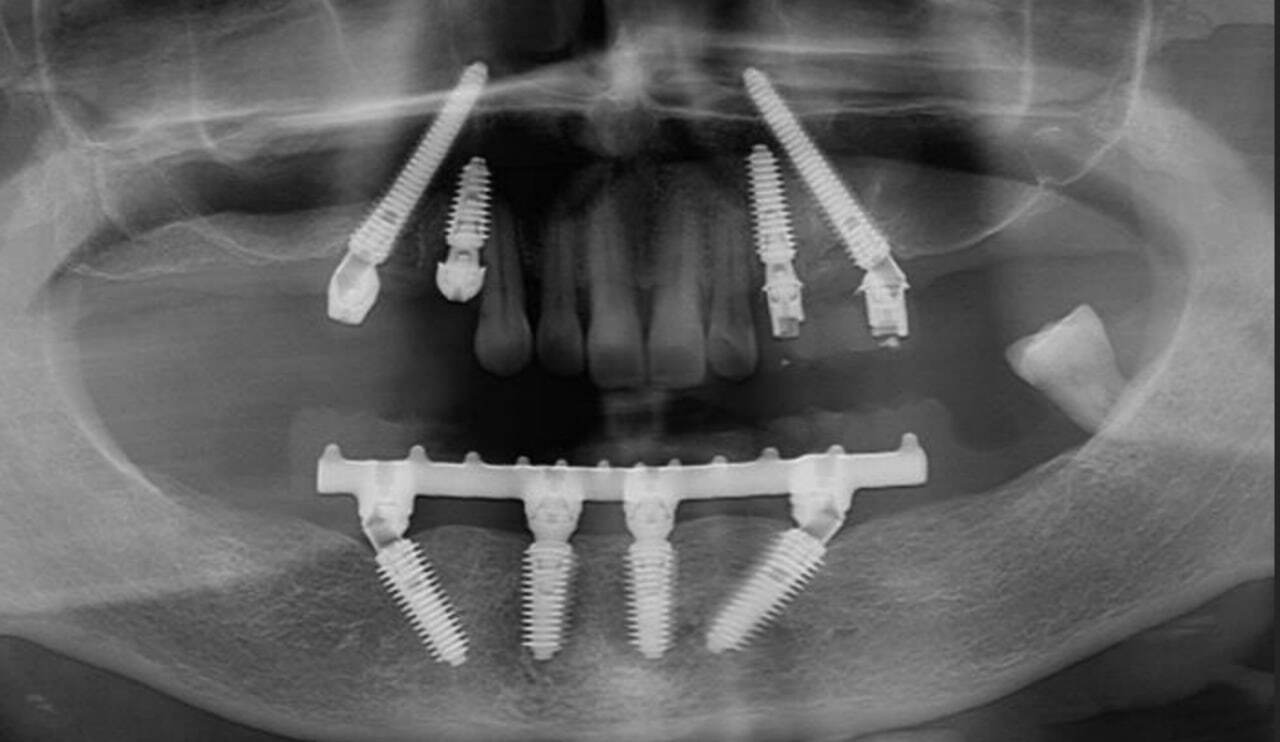

Рентген-контроль полной работы.